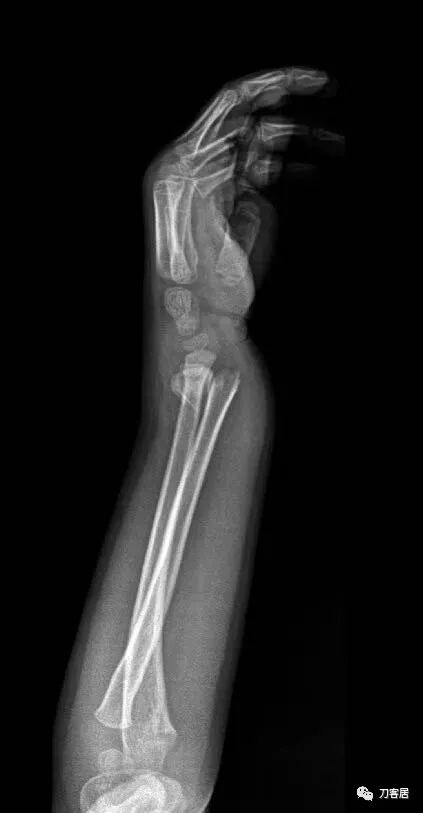

下面为师东良医生提供的病例:

超声引导下闭合手法复位石膏外固定治疗7岁患儿尺桡骨远端移位双骨折。

男,7岁,左前臂远端桡尺骨双骨折,术前X光片见图1,行超声引导下闭合复位石膏外固定术,康复训练,6周拆石膏,随访2.5月的效果。术后2.5X光片见图23。功能上仅前臂旋后较健侧减小15°,继续加强康复训练中。家长满意,评价见图4

2. 超声引导下闭合复位石膏外固定术后2.5月左前臂正位X光片

3. 超声引导下闭合复位石膏外固定术后2.5月左前臂侧位X光片